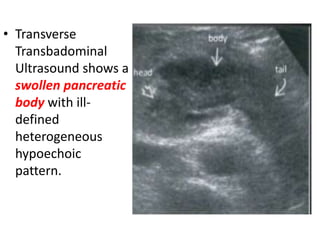

• Transverse

Transbadominal

Ultrasound shows a

swollen pancreatic

body with ill-

defined

heterogeneous

hypoechoic

pattern.